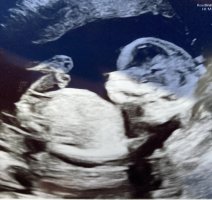

Gjetter guttNoen som vil gjette kjønn? 13+2. Jeg spurte jordmor, hun ville ikke svare fordi hun mente det ikke var tydelig nok. Synes det ene bildet ser ut som jente, og på det andre ser det ut som en gutt

Jeg tipper og gutt. Skjønner hva du mener, at det ser litt flatere ut på det ene bildet, men likevel, hvis du følger kurven til ryggraden, så er vinkelen kanskje liiiitt for mye til å være jente?Noen som vil gjette kjønn? 13+2. Jeg spurte jordmor, hun ville ikke svare fordi hun mente det ikke var tydelig nok. Synes det ene bildet ser ut som jente, og på det andre ser det ut som en gutt

Jeg syntes dette ser ut som en jente, for på bilde to ser det ut som deler av rumpa ikke er i bilde så da ser det ut som nuben er mindre parallell enn det den er.Noen som vil gjette kjønn? 13+2. Jeg spurte jordmor, hun ville ikke svare fordi hun mente det ikke var tydelig nok. Synes det ene bildet ser ut som jente, og på det andre ser det ut som en gutt

Du skal følge kurven ut mot rumpa, så den er parallell.Jeg tipper og gutt. Skjønner hva du mener, at det ser litt flatere ut på det ene bildet, men likevel, hvis du følger kurven til ryggraden, så er vinkelen kanskje liiiitt for mye til å være jente?

Det er 100% en jente. Du har to hvite streker godt synlig. På min private ultralyd så forklarte legen at man så kun disse to strekene på jentebarn. Grunnen til at du tror det er gutt på bildet 2 er stillingen til barnet. Hun sitter og derfor peker nub litt opp.Noen som vil gjette kjønn? 13+2. Jeg spurte jordmor, hun ville ikke svare fordi hun mente det ikke var tydelig nok. Synes det ene bildet ser ut som jente, og på det andre ser det ut som en gutt